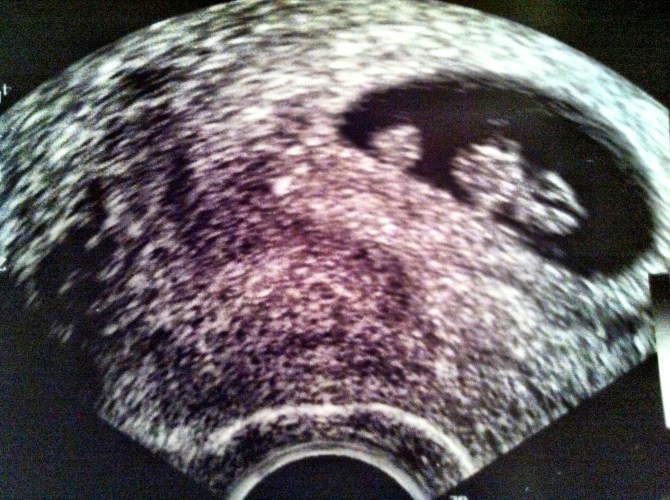

You had a long hectic day and you barely had time to think about what’s growing in your belly? Time to roll in bed and relax while listening to “Bébé d’amour” by Henri Dès, a cute song with soft music and sweet lyrics, perfect for bonding with baby…